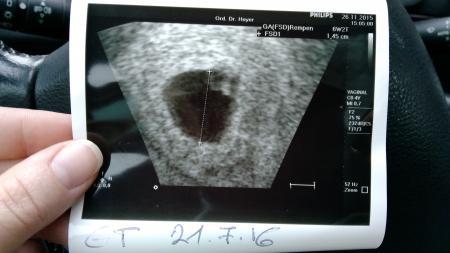

Hallo Bin ganz neu hier und habe bislang nur mitgelesen. Aber mich verlässt langsam die Geduld und ich muss irgendwo hin mit mir! 1. Tag letzte Mens 19.10. Zyklus 26 Tage (oh gott wie kurz, laut meiner FA) Schon 3-4 Tage vor nächster Mens habe ich gemerkt, dass was komisch ist. 1 Tag nach Fälligkeit - positiv!!! Nächste Woche bei FA auch positiv im Urin, US aber nur mit 2 Stellen "vielleicht wird da noch was draus" ,Blut abgenommen, nächster Termin jetzt am 4.12..... und die Zeit vergeht nicht und ich weiß nicht ob ich mich freuen oder Angst haben soll. Traue mich keinem davon zu erzählen, außer meinem Mann natürlich und da wo es sich nicht vermeiden lässt. Wäre Freitag bei 6+4 ... meint ihr wir bekommen dann Klarheit? Würden es am WE so gerne den Eltern erzählen.... Ich Hoffe ihr nehmt mich in die Runde auf und könnt mir Hoffnung machen, dass wir bald Gewissheit haben! Ganz liebe Grüße!!!!

Hallo und herzlichen Glückwunsch vil. Sieht man ja das herzchen schlagen, ich war bei 6+2 und man konnte einen Herzschlag erkennen liebe grüße und alles gute

Bild zu